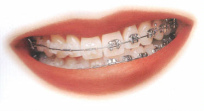

Grund: Zahnspangenklammern

(Brackets)

-- Zahnfleischrückgang ist möglich durch die Zugkräfte

von Zahnspangenklammern: So kann sich das Zahnfleisch

zurückziehen [3]

Brackets können durch die Zugkräfte

einen Zahnfleischrückgang provozieren [3].

Ausserdem muss sich das Zahnfleisch anpassen

und eventuell werden die Zahnfleischtaschen

grösser, so dass die Gefahr für

Zahnfleischentzündung wächst. Also ist nach

einer Brackets-Therapie die beste Zahnpflege

angesagt, mit Zahnseide mindestens einmal pro

Woche [7]. |